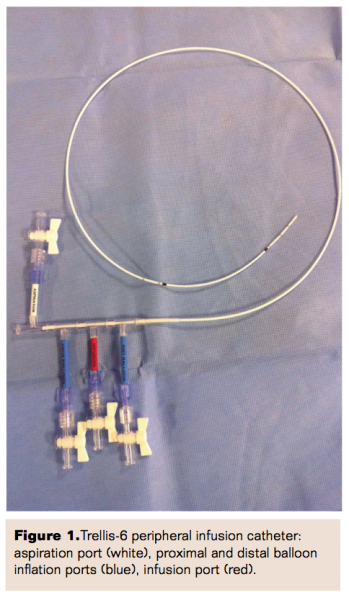

The Trellis Peripheral Infusion System is designed to treat arterial beds with acute/subacute thrombotic occlusions and is comprised of an oscillation drive unit (ODU), a side-hole infusion catheter with occlusion balloons anchored on each end, through which the thrombolytic agent can be delivered to the isolated segment of the vessel without systemic effects (Figure 1). Traditionally, the device is advanced over a standard 0.035˝ wire to the target lesion. Once in position, the balloons of the device are inflated to isolate the treatment zone and a desired dose of tissue plasminogen activator (tPA) is infused into this localized area. The 0.035˝ guidewire is then removed, the device oscillating wire is introduced, and the Trellis is powered on from the ODU. Once the intended duration of treatment is completed, the wire is removed and aspiration is performed through the port designed for this purpose. The proximal and distal balloons are deflated in a sequential fashion and the device is removed. This is followed by treatment of any residual disease in the affected vessel or vessels by way of percutaneous transluminal angioplasty (PTA) with provisional stenting.